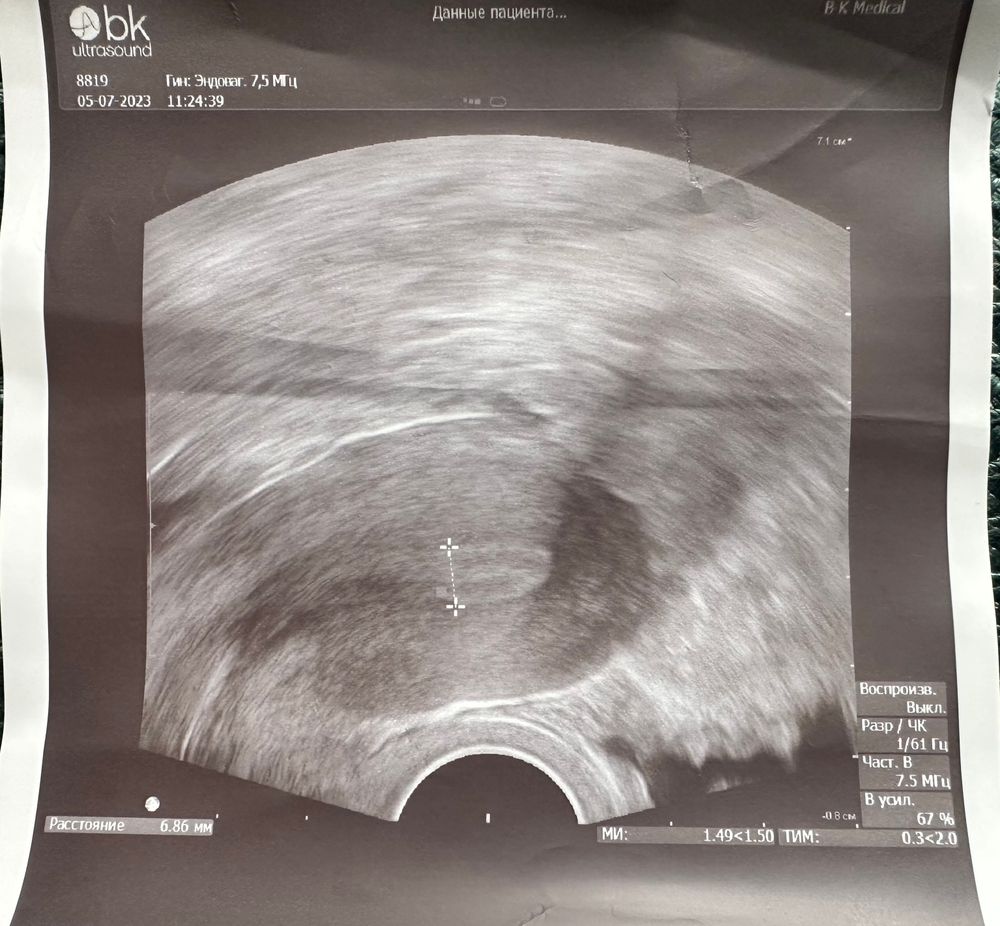

девушки,сегодня 13 дц в крио,была на узи,сказала эндометрий не очень по мм,но красивый.

Сказала три разных толщины,прямо и растянуть если сильно.

итог: 5,59 мм; 7,53мм; 6,86мм

Так вот какой верный то?Как понимать если надежда,что дорастет до 8мм хотя бы?Я так и не поняла.

фото прикрепляю,все за один сеанс